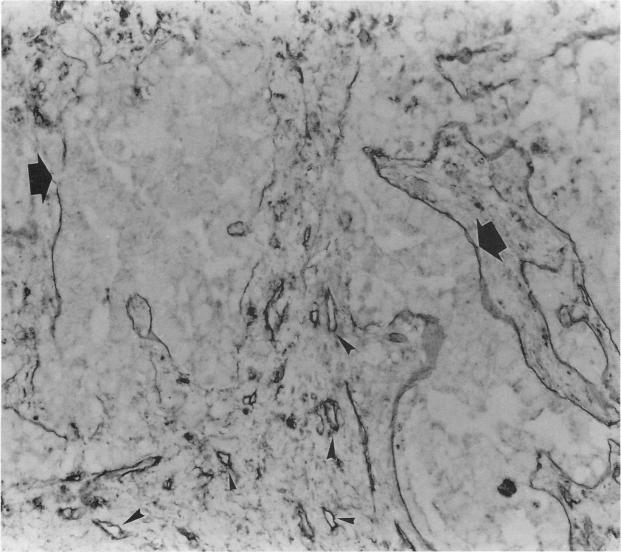

Tumour cells in 23 (82%) cases reacted to cathepsin B: 13 cases were weakly positive and 10 were strongly positive. Laminin in tumour associated basement membrane produced various staining patterns: two cases had an almost continuous distribution of laminin in tumour associated basement membrane in the tumour tissues, while a moderately discontinuous laminin distribution pattern was found in 12 cases, and a highly fragmented pattern was found in 14 cases. The degree of cathepsin B expression in tumour cells was significantly correlated with the break up of laminin staining. In some cases a discontinuous pattern of tumour associated laminin was frequently observed adjacent to cathepsin B positive tumour cell nests.

23例(82%)病例的肿瘤细胞对组织蛋白酶B有反应:13例弱阳性,10例强阳性。肿瘤相关基底膜中的层粘连蛋白呈现出各种染色模式:2例肿瘤组织中肿瘤相关基底膜中层粘连蛋白几乎呈连续分布,12例呈中度不连续分布模式,14例呈高度碎片化模式。肿瘤细胞中组织蛋白酶B的表达程度与层粘连蛋白染色的断裂显著相关。在某些病例中,在组织蛋白酶B阳性肿瘤细胞巢附近经常观察到肿瘤相关层粘连蛋白的不连续模式。